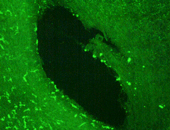

In den letzten Jahren wurde es nämlich zunehmend klar, dass Zellen des Immunsystems bei der Übertragung der PrPsc aus dem Darm in das zentrale Nervensystem eine wesentliche Rolle spielen. Die Innsbrucker Arbeitsgruppe hatte im Rahmen von anderen Untersuchungen über die Entstehung der Atherosklerose schon früher entdeckt, dass in der innersten Schicht von gesunden menschlichen und tierischen Arterien ein bisher unbekanntes Netzwerk von sehr wichtigen immunstimulierenden Zellen, den sogenannten vaskulär assoziierten dendritischen Zellen (VADC) vorhanden ist, von dessen Existenz an diesem ungewöhnlichen Ort man bisher nichts wusste. Da dendritische Zellen die Fähigkeit haben, im Körper aktiv umherzuwandern und aufgenommenes Fremdmaterial den Zellen des Immunsystems zu präsentieren, wurde bei den Versuchen der Arbeitsgruppen gemeinsam der Frage nachgegangen, ob derartige VADC die gefährlichen PrPsc beherbergen können. Dabei konnte gezeigt werden, dass dendritische Zellen in der Wand von Gehirnarterien von Patienten mit vCJD grosse Mengen von PrPsc enthalten. Die Autoren schließen aus diesen Befunden, dass dendritische Zellen, die in vielen anderen Körperregionen - so auch im Magen-Darmtrakt - in hoher Dichte vorkommen, die "trojanischen Pferde" darstellen könnten, welche PrPsc vom Darm in das zentrale Nervensystem transportieren. Wenn es gelingt, dieses Konzept durch funktionelle Untersuchungen bei Versuchstieren zu untermauern, ergeben sich völlig neue Gesichtspunkte für die Diagnose, Prävention und vielleicht auch Therapie dieser gefürchteten Erkrankung.